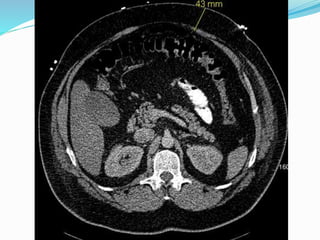

Parastomal hernia

 Incidence is unknown

due to underreporting

and difficult dx.

 Estimated to be between

20-80%

 More frequent with

colostomy than

ileostomy

 Cingi et al

 23 patients

 Patient examination

(PE) detected PSH in

52%

 CT detected total of

78%